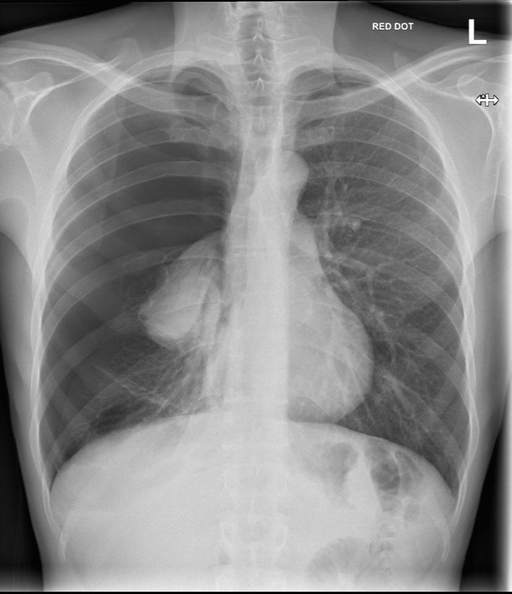

A chest X-ray is ordered and this is shown below:

What is the best management option for this patient?

Chest drain insertion

This patient has features of a secondary spontaneous right-sided pneumothorax, most likely secondary to her underlying COPD.

Patients who have a secondary pneumothorax who are symptomatic or have a pneumothorax measuring >2 cm from the chest rim on radiographs should be offered a chest drain.